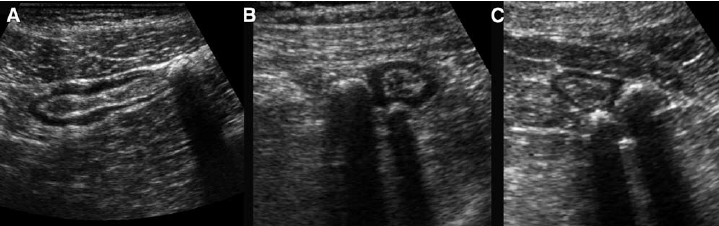

“Sonographic features of uncomplicated diverticulitis: diverticula appear as bright “ear” out of the bowel wall (a); a central shadowing echogenicity may indicate the presence of fecalith (b).”

Source: https://theultrasoundjournal.springeropen.com/articles/10.1186/2036-7902-5-S1-S5

“( A , B , C ) Sigmoid diverticulosis in three asymptomatic patients. The fecalith-filled diverticula are recognized as strongly reflective, round structures casting an acoustic shadow and localized at the outer contour of the empty sigmoid. The thin wall of the diverticulum, consisting of mucosa only, is not separately visible.”

Source: Puylaert, Julien. (2003). Ultrasonography of the acute abdomen: gastrointestinal conditions. Radiologic clinics of North America. 41. 1227-42, vii.